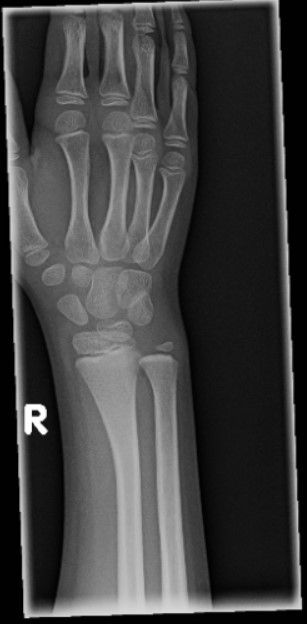

The patient is an 11-year-old boy who presents complaining of pain in his left and right forearm and wrist after falling from a height of approximately 5 feet. His parents report that he was attempting to hang upside down by his knees from a chin-up bar in his school’s gymnasium when he slipped.

View the images taken and consider what the diagnosis and next steps would be. Resolutions of the case is described on the next page.

An 11-Year-Old Boy with Forearm and Wrist Pain After a Fall